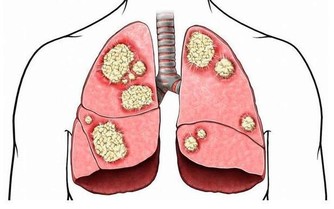

此外,需要注意的是,孕婦需要密切關注自己的血紅蛋白含量,太低需要及時給予干預。

孕婦缺鐵會直接影響胎兒的智力發育,使孩子智力遲緩,而且這種情況往往是不可逆的,

及時長大了補充再多的鐵元素也不能夠逆轉智商不足的困境。